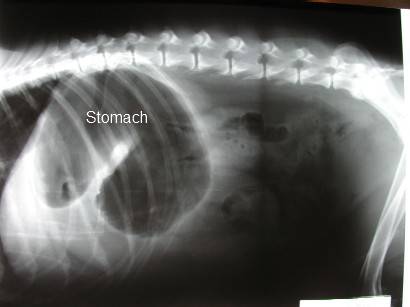

Okrem symptómov torziu žalúdka spoľahlivo preukáže rtg brušnej dutiny, po ktorom nasleduje stabilizácia pacienta a rýchla operácia, pri ktorej sa uvoľní tlak v žalúdku, ako aj tlak na ostatné orgány tým, že sa z neho pri otvorení vypustia plyny a následne sa vyčistí. Pri zákroku sa zistí aj miera poškodenia žalúdočných stien a skontroluje sa aj stav sleziny. Ak je žalúdok v poriadku, vráti sa na miesto a prišije, čím sa znižuje riziko recidívy (z 50% až 60% na 12% až 24%), nie je však zriedkavosťou, že psovi, ktorý už torziu prekonal, sa tento stav vráti.